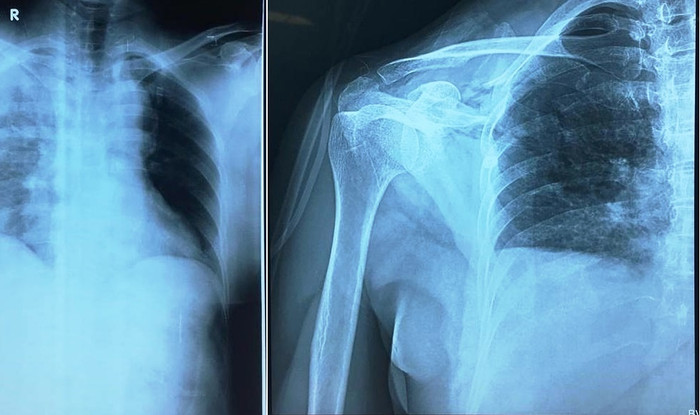

Bệnh nhân được chẩn đoán: Đa chấn thương, shock mất máu/ suy hô hấp tràn máu tràn khí màng phổi bên Phải do vết thương thấu ngực/ nhóm máu O Rh(-).

Tiếp tục đặt ống nội khí quản gây mê toàn thân, vừa đánh giá vừa xử trí các vết thương cụ thể: vết thương thấu ngực do dao đâm từ bả vai (P) xuyên từ sau ra trước gây tổn thương rách da 10 cm, gãy xương vai, đứt lìa ba xương sườn 4,5,6 gây tràn máu, tràn khí màng phổi (P).

| Ảnh chụp phim X - quang bệnh nhân (Ảnh: Bệnh viên đa khoa Đức Giang cung cấp) |